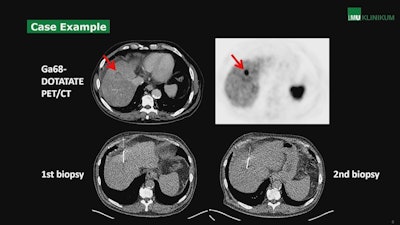

According to the results, SSR-positive metastatic hepatic involvement on PET/CT was reported in 98.6% (n = 145) cases, while histopathology showed hepatic involvement of NETs in 92.5% (n = 136) of cases. In 7.5% (n = 11) of cases, histopathology was negative, despite suspected liver metastases in SSR-PET/CT scans. In addition, in seven of 11 cases in which a second biopsy was available, SSR-PET/CT confirmed findings of liver metastases in five cases, while two of the rebiopsies confirmed the negative histopathologic results, Fabritius noted.

Ultimately, the positive predictive value (PPV) of SSR-PET/CT for detecting liver metastases was excellent at 92.4%, but even higher at 95.9% when compared with histopathology and rebiopsy, according to the study.